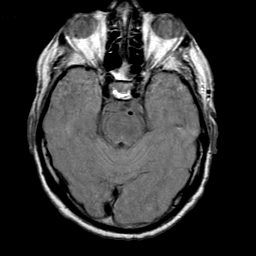

Meningioma, MR Study #1 -- Slice #6

[Home][Help][Clinical] Slice 6